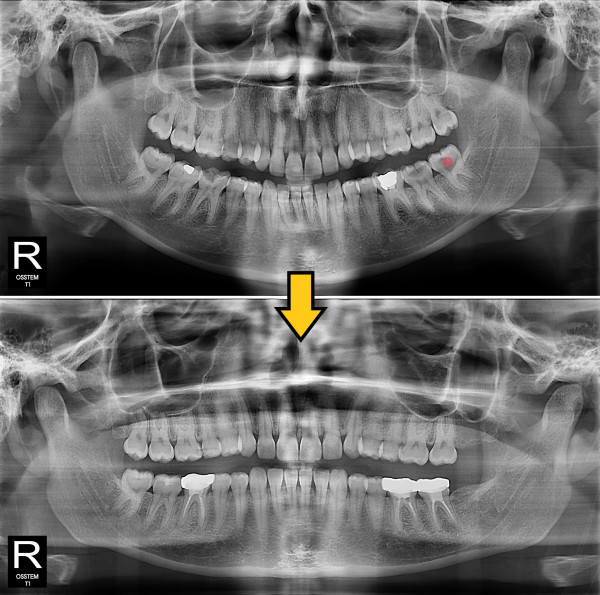

사랑니발치 충치가 심한 사랑니